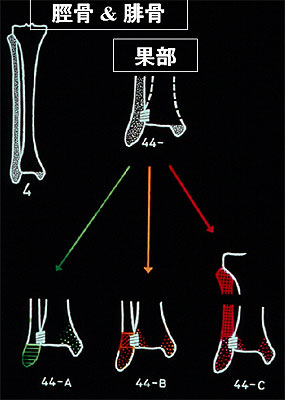

足関節骨折 一般社団法人 日本骨折治療学会 骨折の解説

足関節骨折 一般社団法人 日本骨折治療学会 骨折の解説

足関節骨折 一般社団法人 日本骨折治療学会 骨折の解説

足関節骨折 一般社団法人 日本骨折治療学会 骨折の解説